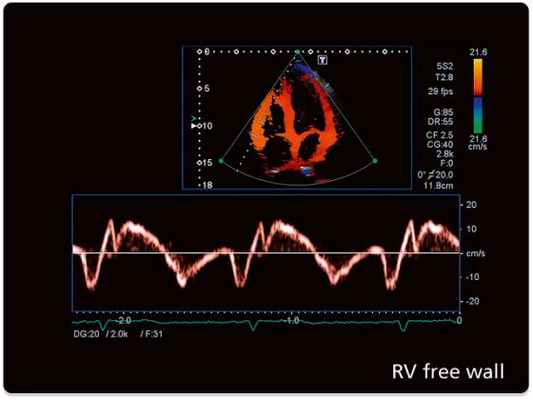

Тканевый допплер (Tissue Velocity Imaging). Принцип данного метода основан на картировании направления движения тканей определенным цветом. Таким образом красным цветом обозначают движение к датчику, синим - от датчика. Изучая направления движения стенок левого и правого желудочков в систолу и диастолу с помощью TVI можно обнаружить скрытые зоны нарушения локальной сократимости. Совмещение двухмерного исследования в режиме TVI с M-модальным увеличивает точность диагностики.

Тканевой импульсный допплер (Pulsed Wave Tissue Velocity Imaging). Позволяет оценить графически характер движения стенки желудочков в конкретной данной точке. Выделяют систолический компонент, ранний и поздний диастолический компоненты.Данный вариант допплера позволяет проводить картирование миокарда и увеличивает точность диагностики у больных с ишемической болезнью сердца.